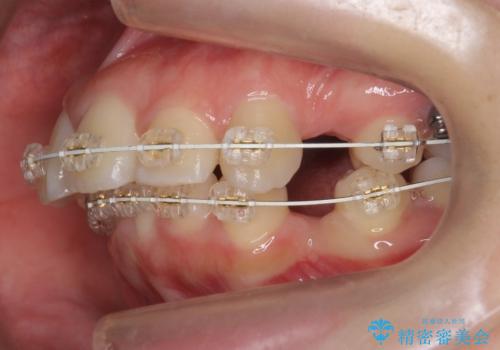

- 矯正装置

- 審美装置

- 治療計画

口元を下げたいとのことで、歯を抜いてワイヤー矯正を行いました。

上下左右の小臼歯を抜歯しています。